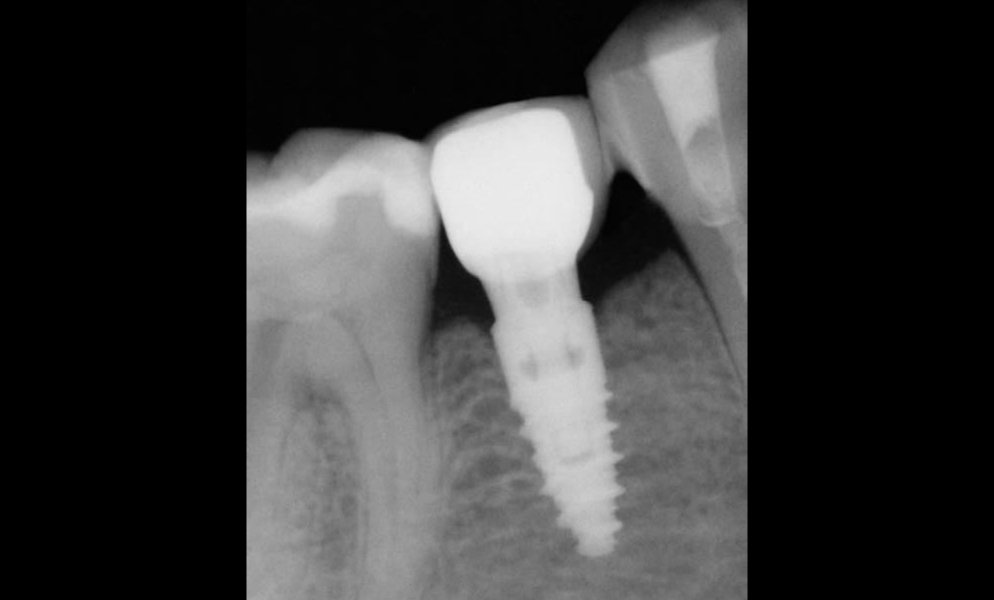

| Before | After |

![]() |

| Single posterior tooth missing space restored with a 4x6 mm short dental implant (Bicon, USA) to avoid sinus lift and bone graft procedures | |